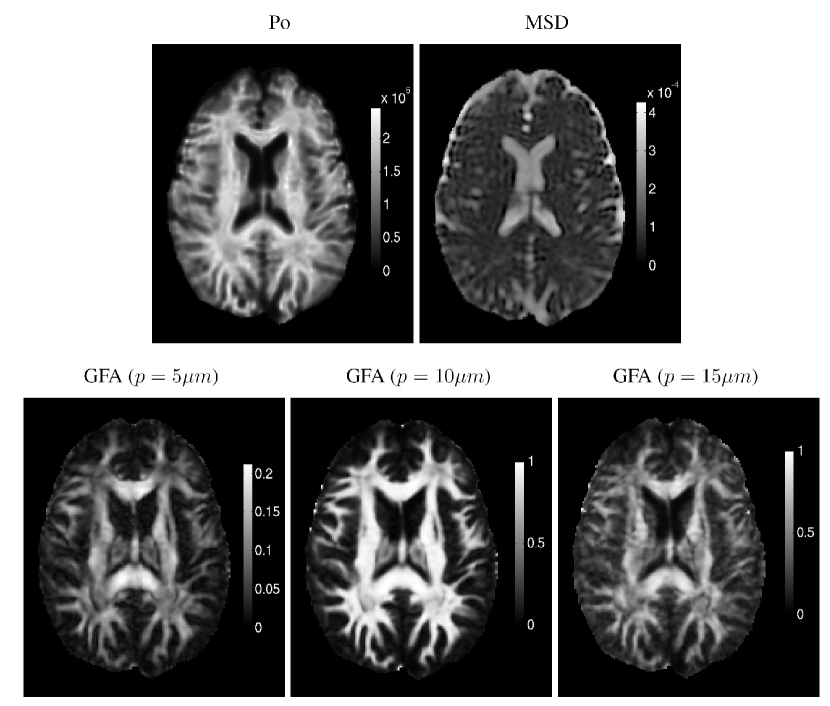

Next, we illustrate the atlas estimated from the 363636 adults’ HYDI datasets after ten iterations. Figure 2 illustrates the estimated atlas of the diffusion signals at shells of b=300,1200,2700,4800,7500​s/m​m2𝑏3001200270048007500π‘ π‘šsuperscriptπ‘š2b=300,1200,2700,4800,7500s/mm^{2}. Figure 3 shows the reconstructed EAP based on the coefficients of HYDI. Each row respectively shows the estimated atlas in the axial, coronal, and sagital views, while each column shows the zero displacement probability (Po) image derived from EAP and the diffusion profiles of this atlas at three layers of the EAP space. Figure 4 demostrates the estimated altas on the zero-displacement probability (Po), mean squared displacement (MSD), and generalized fractional anisotropy (GFA) under three different radii, as introduced in [14]. Visually, these figures show that the estimated atlas has the anatomical details of the brain white matter.

Figure 4: Illustration of the estimated altas on the zero-displacement probability (Po), mean squared displacement (MSD), and generalized fractional anisotropy (GFA).